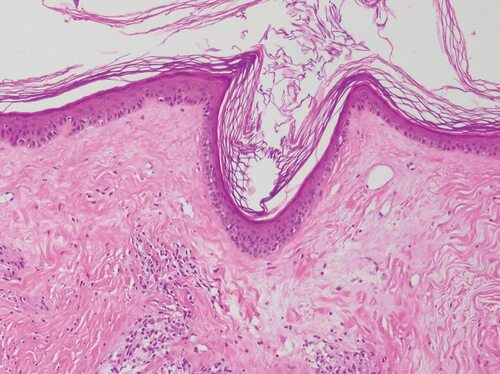

Склеротический Лихен гистология

Склероатрофический Лихен вульвы гистология

Склерозирующий Лихен гистология

Склероатрофический Лихен гистология